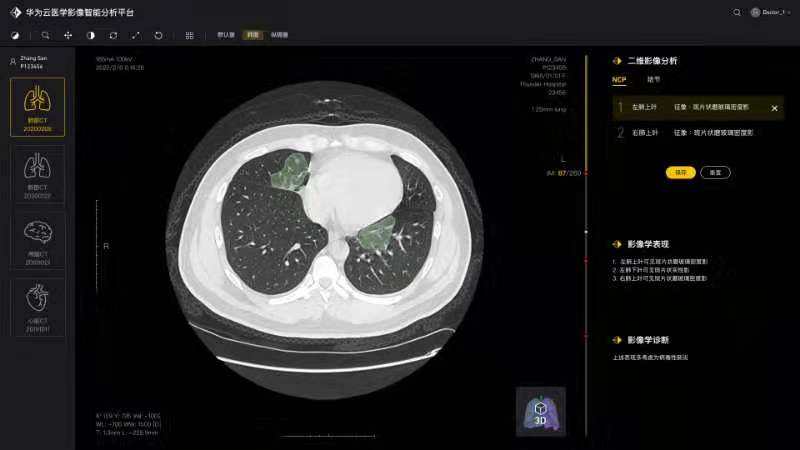

白翔、许永超等老师负责的华中科技大学—华为智能创新实验室积极发挥自身优势,组织团队师生争分夺秒抓紧开展高质量科研攻关,与附属协和医院放射科、华为云、篮网科技等团队共同研发出一套基于人工智能技术的面向新冠肺炎肺部CT影像量化分析系统。2月29日下午,中共中央政治局委员、国务院副总理孙春兰率中央指导组来校考察疫情防控科研攻关情况,许永超副教授当场向孙副总理介绍了研发推出该系统的工作及成果。该系统可以辅助医生更高效地区分新冠肺炎的早期、进展期与重症期,有利于早期筛查与防控。同时,对于确诊病人,基于对多次复查影像数据的量化分析,医生能够有效评估病情进展及用药疗效等情况。目前该系统已在全国几十家医院使用,日均调用量3000多次。孙春兰肯定了研究团队所开发系统的精确性,可以辅助医生定量分析,大幅提升效率,缓解影像医生的压力。她非常关注该系统的落地应用情况,特别是在湖北省、武汉市的应用,鼓励团队结合CT影像与核酸试剂等信息,进行更为精准的新冠肺炎诊断。